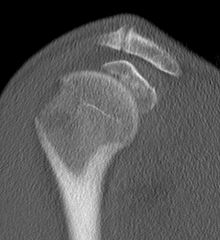

proximal humerus fracture Background ORIF with locking plate Arthroplasty Greater tuberosity fractures Lesser tuberosity fractures / avulsions Book traversal links for Proximal humerus fractures ‹ Pectoralis Major Tears Up Background ›